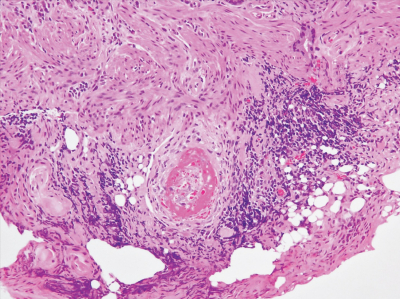

尿所見:蛋白1+、潜血1+、沈渣に赤血球 10〜20/1視野。血液所見:赤血球 352 万、Hb 11.8 g/dL、Ht 32 %、白血球 12,500(桿状核好中球 10 %、分葉核好中球 63 %、好酸球1%、好塩基球1%、単球2%、リンパ球 23 %)、血小板 18 万。血液生化学所見:総蛋白 6.6 g/dL、アルブミン 4.2 g/dL、尿素窒素 28 mg/dL、クレアチニン 1.7 mg/dL、血 糖 96 mg/dL、HbA1c 5.2 %(基準 4.6〜6.2)、Na 136 mEq/L、K 4.2 mEq/L、Cl 99 mEq/L。免疫血清学所見:CRP 6.2 mg/dL、抗核抗体陰性、MPO-ANCA 62 U/mL(基準 3.5 未満)、PR3-ANCA 3.5 U/mL 未満(基準 3.5 未満)。胸部エックス線写真で異常を認めない。入院翌日の夜に下血があり下部消化管内視鏡検査を施行したところ、上行結腸に潰瘍を認め、生検を行った。生検組織の H-E 染色標本 を示す。